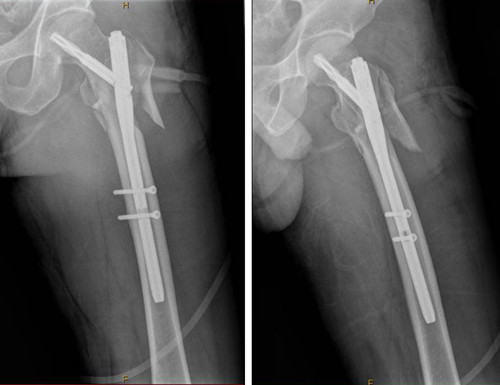

据了解,一个星期前,48岁的张先生在工作中不慎摔倒在地,左髋部受伤严重,入住外一科。经X线查看,彭先生左股骨转子下粉碎性骨折。针对彭先生的伤情,外一科骨科专家团队对治疗方案进行了慎密的思考和设定,外一科团队顺利为张先生完成了“左股骨转子下骨折切开复位PFNA内固定术”。整个手术过程约1小时。术后第2天张先生已经可以坐起,第5天已可坐在床边活动左腿,第7天就能将左腿抬离床面,左腿功能也迅速得以恢复。

外一科主任蔡厚洪介绍说:PFNA技术是一种融合了微创技术的内固定手术方式。该类手术由于其手术创伤小、手术时间短、术间出血少、术中术后并发症发生率低、骨折愈合时间短力学稳定性高等优势,病人能够早期自主配合康复锻炼,临床疗效非常满意。

术后X线